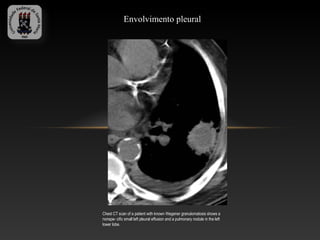

Envolvimento pleural

Chest CT scan of a patient with known Wegener granulomatosis shows a

nonspe- cific small left pleural effusion and a pulmonary nodule in the left

lower lobe.

Envolvimento pleural Chest CTscan of a patient with known Wegener granulomatosis shows a nonspe- cific small left pleural effusion and a pulmonary nodule in the left lower lobe.